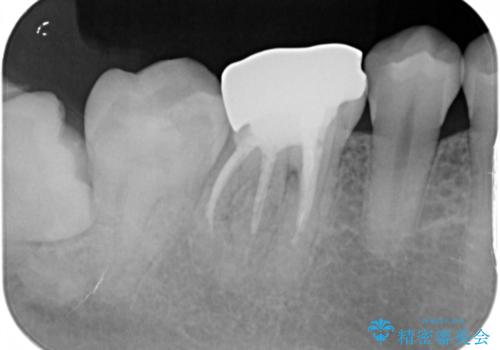

メタルインレーが一部欠けており、その下には大きな虫歯ができていました。

再精密根管治療もご提案しましたがご希望されなかったため、今回は土台と被せ物のみ治療介入しました。

根管治療をした歯は神経のある歯と比較して強度が下がり、長期的に破折のリスクが高まると言われています。破折のリスクを軽減させるため、根管治療を行った歯に対しては歯冠をすべて覆うクラウンという被せ物にて補綴処置を行います。

右上の被せ物についても今後治療介入していく予定です。